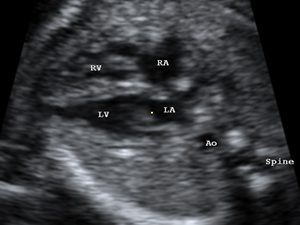

Heart